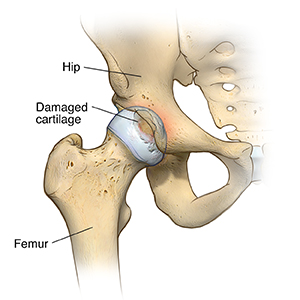

Osteoarthritis. This is a degenerative joint disease that affects mostly middle-aged and older adults. It may cause the breakdown of joint cartilage and adjacent bone in the hips.

Rheumatoid arthritis. This type of arthritis causes inflammation of the synovial lining of the joint. It causes extra synovial fluid and joint destruction. It may lead to severe pain and stiffness.

Traumatic arthritis. This arthritis is caused by an injury. It may also damage the hip cartilage.

Osteoarthritis causes loss of joint cartilage in the hip. Damage to the cartilage and bones limits movement and may cause pain. People with severe pain from degenerative joint disease may not be able to do normal activities that involve bending at the hip. These activities include walking and sitting.

Other forms of arthritis, such as rheumatoid arthritis and arthritis, that results from a hip injury can also damage the hip joint. So can avascular necrosis. This is loss of blood supply to the head of the femur. Childhood hip diseases that can cause arthritis as an adult can also damage the hip.